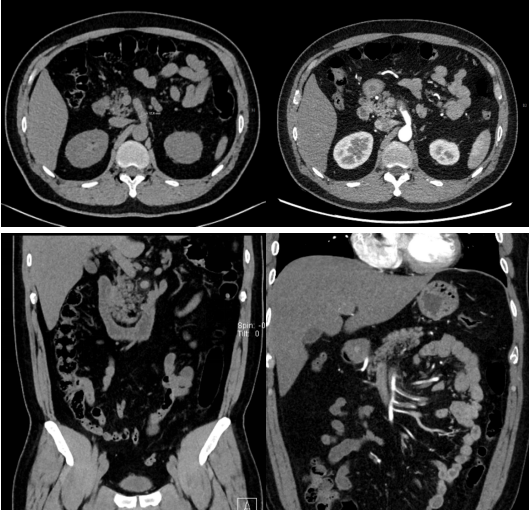

当晚19时,苏州高新区人民医院急诊科接诊一名44岁男性患者。该患者因“突发腹部剧烈绞痛3小时”就诊,既往有高血压、高血脂病史,未规律治疗。急诊科紧急申请腹部CT平扫,放射科迅速启动夜间应急流程,在完成快速扫描后立即进行阅片分析。在观察血管区域时,发现肠系膜上动脉管径明显增宽,最宽处约12mm,管腔内密度不均,管壁欠光整,周围脂肪间隙模糊。结合患者有高血压、高血脂高危因素及急性剧烈腹痛的临床表现,高度怀疑肠系膜上动脉栓塞。放射科立即与急诊科沟通,建议紧急行腹部CT血管造影(CTA)以明确诊断。

临床迅速启动CTA造影检查。CTA明确肠系膜上动脉主干及其主要分支内见广泛充盈缺损,远端分支显影不良,与平扫所见的动脉增宽征象完全吻合,从而明确诊断为肠系膜上动脉栓塞,并同时排除了其他急腹症。